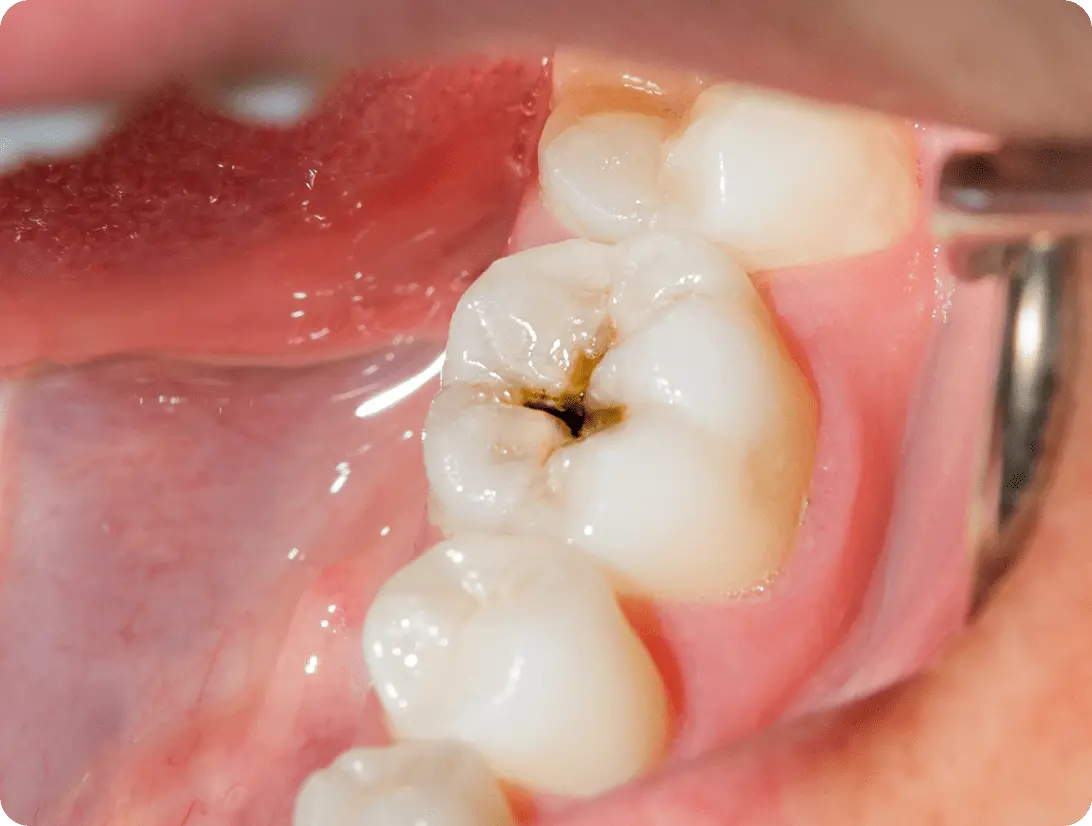

• C2 中度

C2 中度

象牙質にまでむし歯が到達した段階し、温かい・冷たいものがしみる状態です。